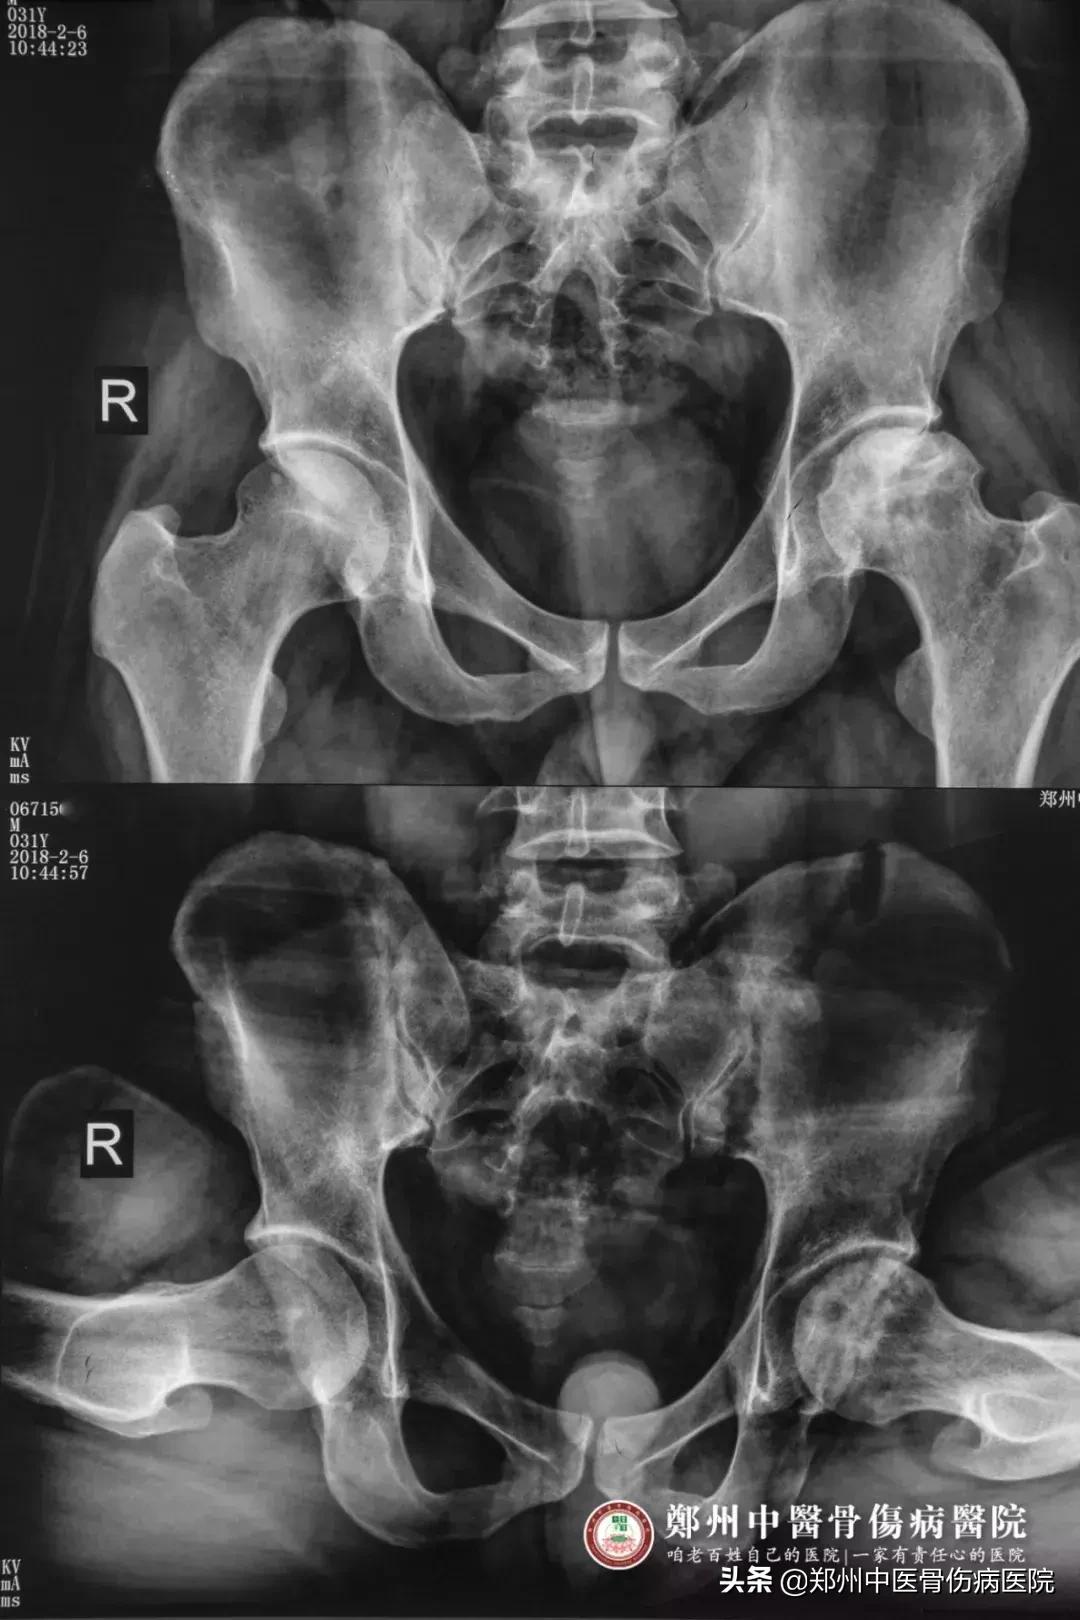

患者片子

听闻朋友介绍,有病友在郑州中医骨伤病医院经过中医中药的综合治疗,已经有了明显的好转。2018年2月,朱先生抱着一颗试试看的心态,慕名来到医院找到龚晓霞主任诊治。通过相关的体格检查及专科检查,朱先生被确诊为“左侧股骨头坏死三期”。

出院后,朱先生按照龚主任的嘱咐,每三个月来院复查一次。复查的结果,一次比一次令人欣喜,从片子上能够明显地看出,左侧股骨头骨质密度较之前有所改善,并且查体时,朱先生屈髋、抬腿功能明显提高不少,种种迹象表明,他的病情在一天天地好转。